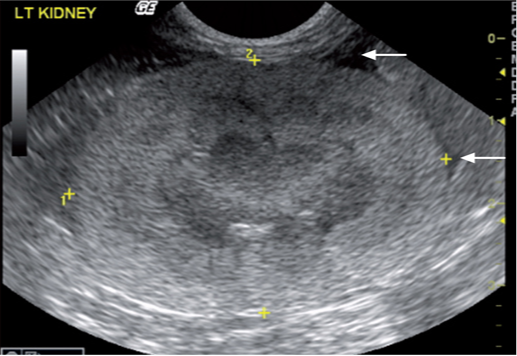

老年猫通常会患有慢性肾脏病(CKD)。患有慢性肾脏病的超声波变化是肾脏较小(<3.2厘米),并且肾脏轮廓不规则、皮质与髓质交界处不清晰,肾实质异质性、肾髓质局灶性或弥漫性过度再生、髓质环征、肾实质梗塞及或钙化(图9 -11.视频4和5)。但如果只有以上的其中一个病征是不足以诊断猫患有慢性肾脏疾病的。在疾病的最后阶段,肾脏会非常小、极不规则,并且其回声结构完全改变,其中可能包括高回声病灶,具有或不具有钙和磷酸盐沉积相对应的声影(图12)。偶尔,由于肾脏的异常结构,这些病患的肾脏只能从其位置识别出来,而不是通过它们显示的正常超声回波结构。有时会观察到所谓的“大肾,小肾”综合征,其病理表现为其中一个肾脏体积明显减小,另一个肾脏体积有所增加。进行肾活检的组织病理学研究是确定导致慢性肾脏疾病病变类型所必需的。重要的是要考虑到超声诊断与肾功能无关,并且这也不是预测猫发展为氮血症的好办法。